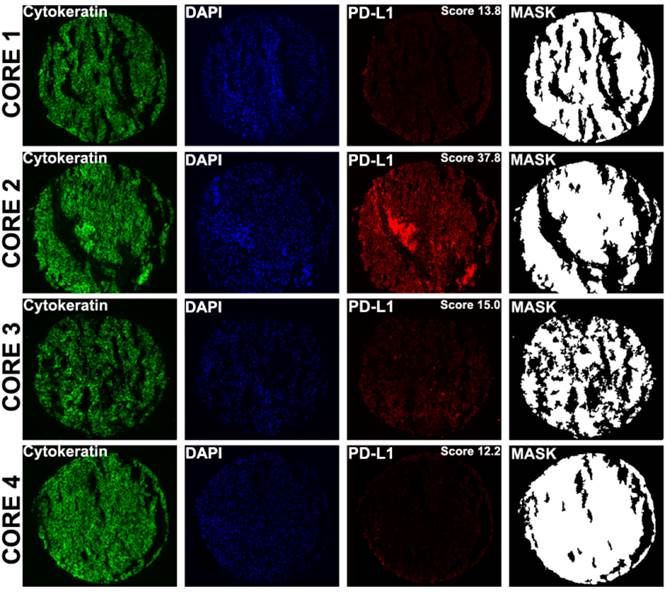

A number of prior reports have suggested that PD-L1 expression within a tumor might be heterogeneous.[25] Seeing that in metastatic patients the only available tumor is often core biopsies rather than whole tissue blocks, we next attempted to determine whether the degree of heterogeneity varies between primary and metastatic sites, using the TMA cores as surrogates for core biopsy specimens. To further quantify the intra-tumor heterogeneity of PD-L1 expression within the primary and matched metastatic tumors utilizing the four different expression measurements for each tumor block, a composite median absolute deviation (MAD) score was generated for each block and patient, as described previously.[22] The Wilcoxon paired, two-sided signed rank test, showed that overall the heterogeneity between primary and metastatic tumors did not significantly differ (P = 0.482) (Figure 3). Figure 4 shows an example of heterogeneous PD-L1 staining of four corresponding primary tumor cores from a patient whose AQUA scores for the four cores ranged from 12.2 to 37.8.

Figure 4

Examples of PD-L1 fluorescent staining, shown at ×10 magnification in four distinct cores from different areas of a primary tumor corresponding to a single patient. AQUA uses cytokeratin to define the tumor mask , DAPI to define the nuclear compartment , and Cy5 for the target (PD-L1). The cytoplasmic compartment is generated by subtracting the nuclear compartment from the cytokeratin mask. PD-L1 expression is then measured within each compartment within the tumor mask, and each spot is assigned a score based on pixel intensity per unit area. PD-L1 expression (measured in the tumor mask compartment) in cores 1 to 4 corresponds to AQUA scores of 13.8, 37.8, 15.0 and 12.2 respectively.